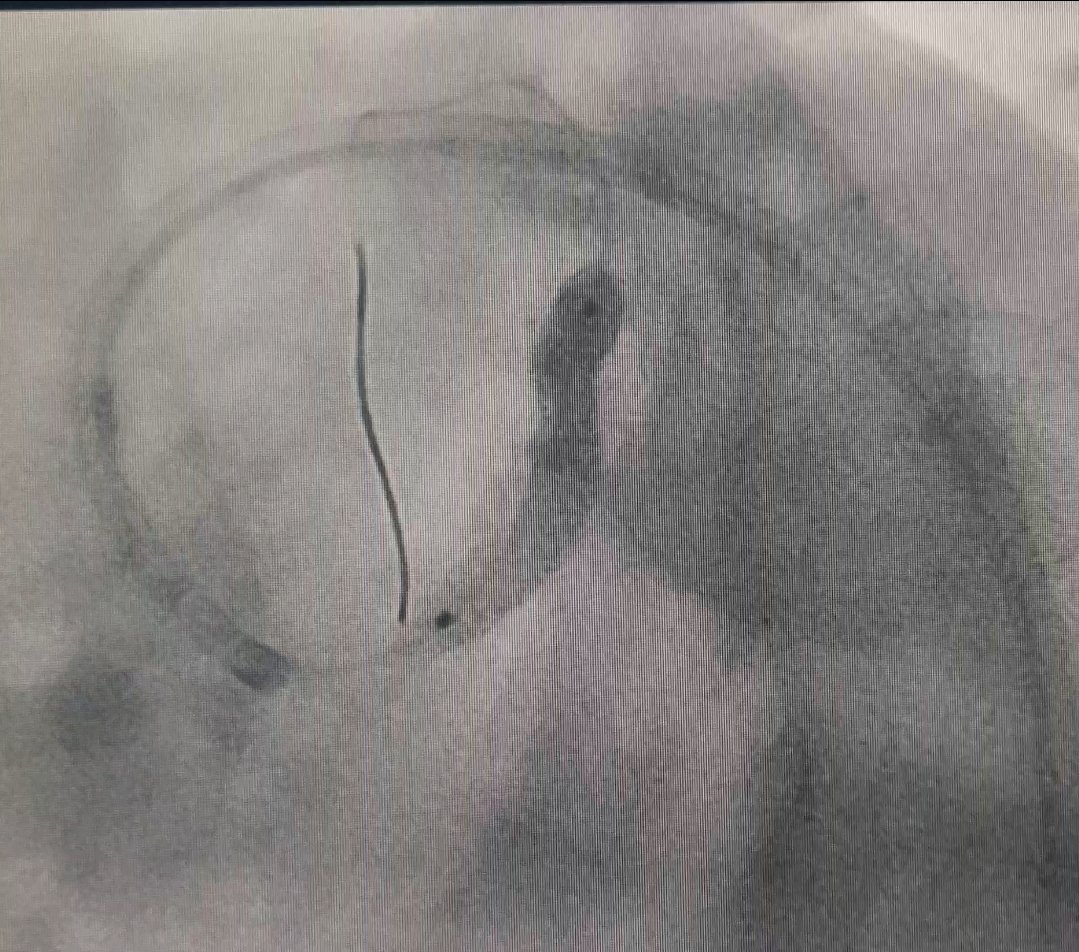

Paciente con #EACMV (#TCI) tratado por #ICP con técnica de #provisionalstent. Resultado exitoso